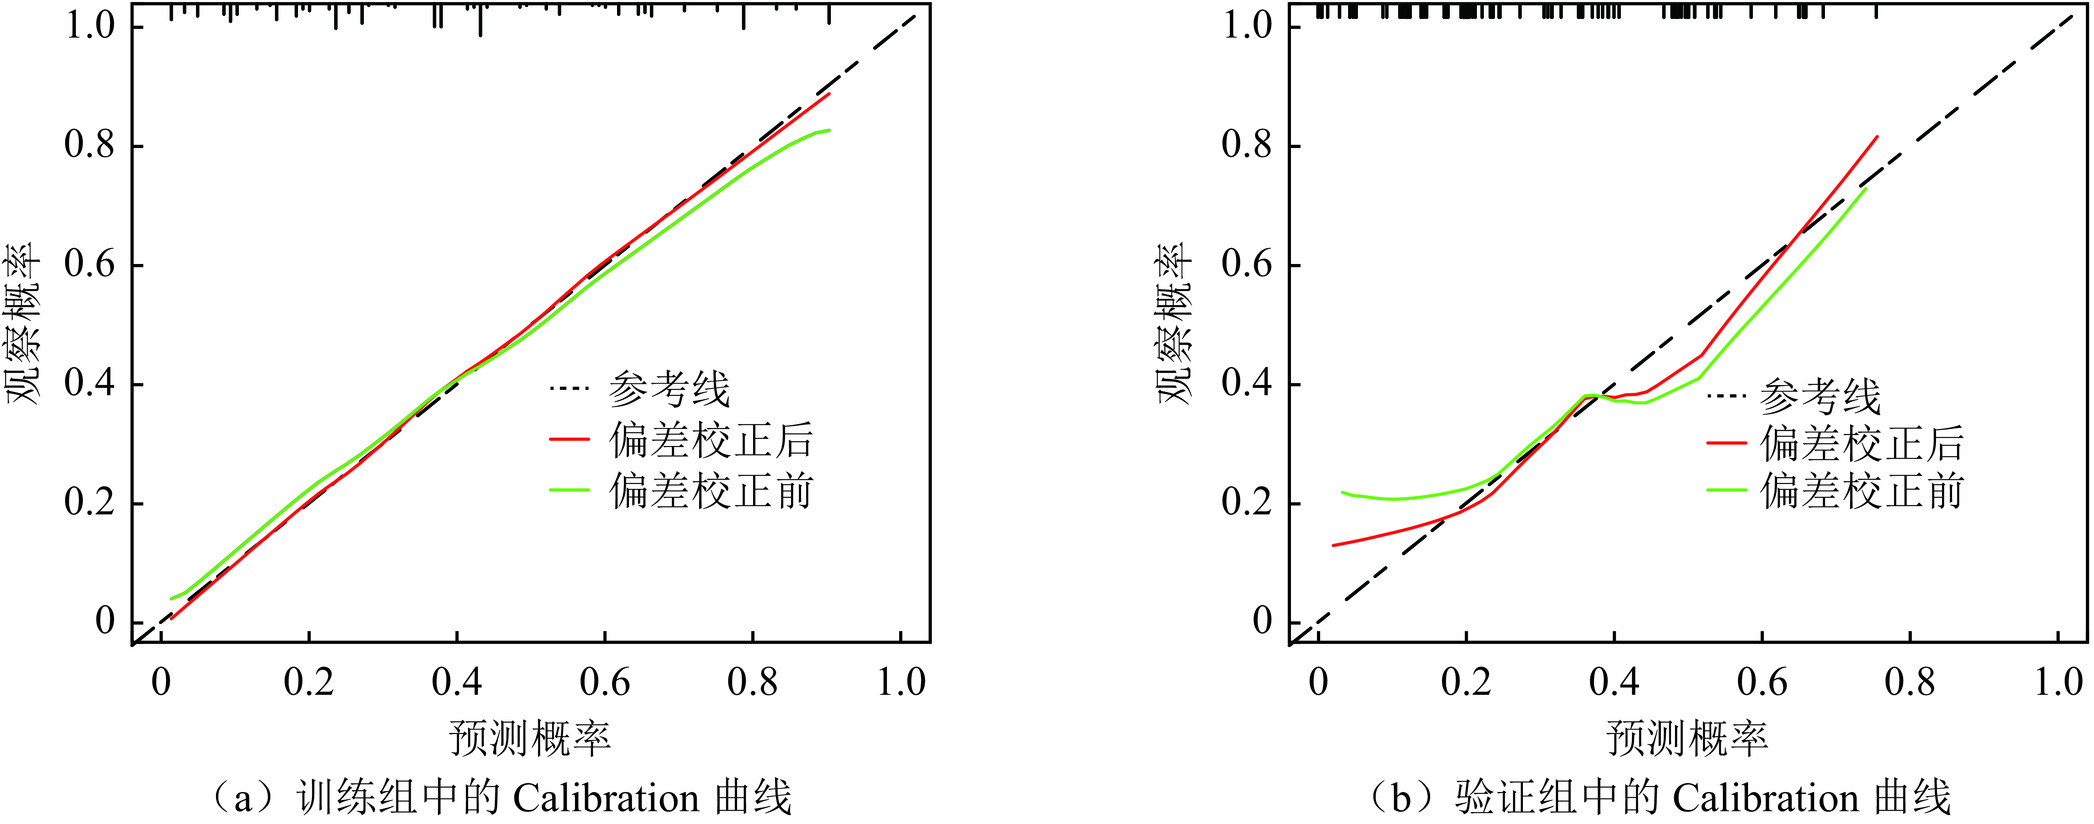

图 3 Nomogram预测CLNM的性能演示(界值为0.303)注:患者1,男性,44岁,PTC病例,CLNM阳性。CT平扫示右叶中下部类圆形病灶,内见钙化,与甲状腺被膜接触约75%(a),增强后不均匀强化(b),超声显示低回声区,境界清晰,边缘光整,约20.6×16.5×18.5 mm(c),对照Nomogram:男性(38分)+年龄 < 55岁(28分)+被膜接触 > 50%(100分)+最大径 > 10 mm(45分)=211分,对应的CLNM预测概率0.73。患者2,女性,37岁,PTC病例,CLNM阴性。右叶内不规则低密度结节,边缘与被膜无接触(d),增强后轻度强化(e),超声显示境界清晰,边缘不光整的低回声区,最大径约8.5 mm(f),对照Nomogram:年龄 < 55岁(28分)+边缘不规则(48分)=76分,对应的CLNM预测概率0.10。Figure 3. Performance of the nomogram for CLNM (cutoff=0.303)Nomogram的预测准确性和临床实用性用Calibration和DCA评价(图4和图5),Calibration显示预测概率和实际概率在训练组和验证组中一致性程度很高。DCA曲线表明,当个体患者预测概率在0.1到0.85范围内,Nomograms预测CLNM的净收益高于无预测组或全部干预组。